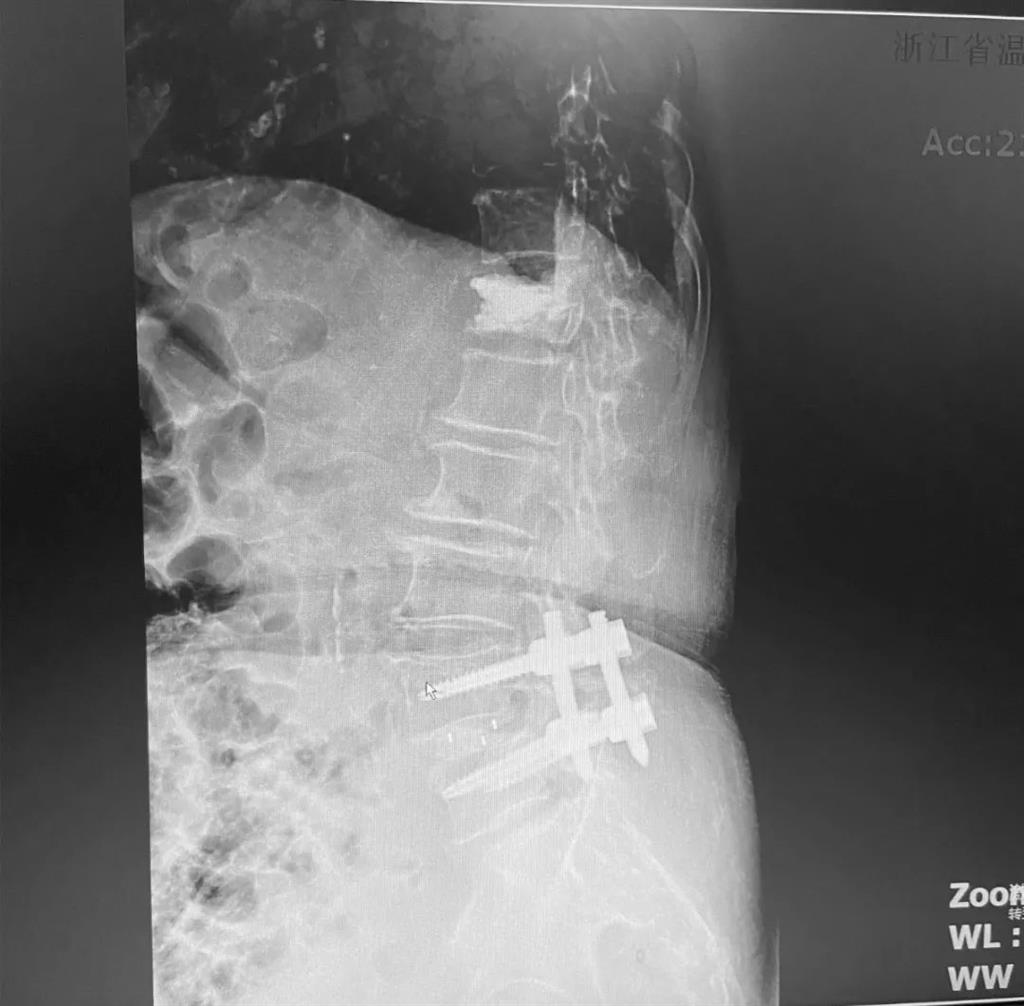

據(jù)了解,脊柱內(nèi)鏡下腰椎融合術(shù)只需要打幾個(gè)“鑰匙孔”即可完成。聽起來是不是很簡(jiǎn)單?在脊柱內(nèi)鏡下,劉丹主任先后為患者進(jìn)行了椎管減壓、椎間盤摘除,再實(shí)施椎弓根螺釘放置、椎體植骨融合內(nèi)固定,一系列步驟有條不紊。

看似簡(jiǎn)單的幾個(gè)步驟,但實(shí)際上很復(fù)雜,需要主刀醫(yī)生有豐富的手術(shù)經(jīng)驗(yàn)和細(xì)致耐心的操作。

術(shù)中只需切開4個(gè)如“鑰匙孔”般大小的孔道